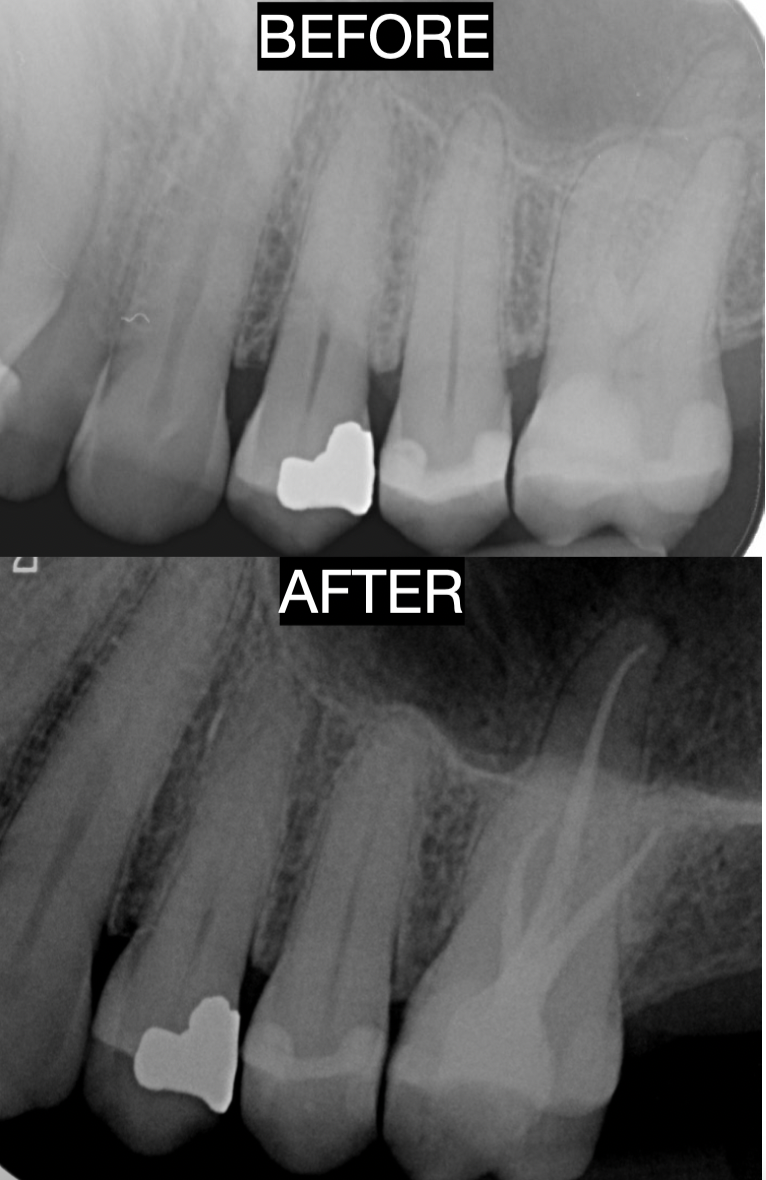

We regularly utilise our wide variety of cutting-edge, state-of-the-art dental technologies to save time and enable painless, hassle-free and affordable dental treatments for our patients. At ADHPL, the patient is held in the highest regard – without the patient, our service would not be possible.